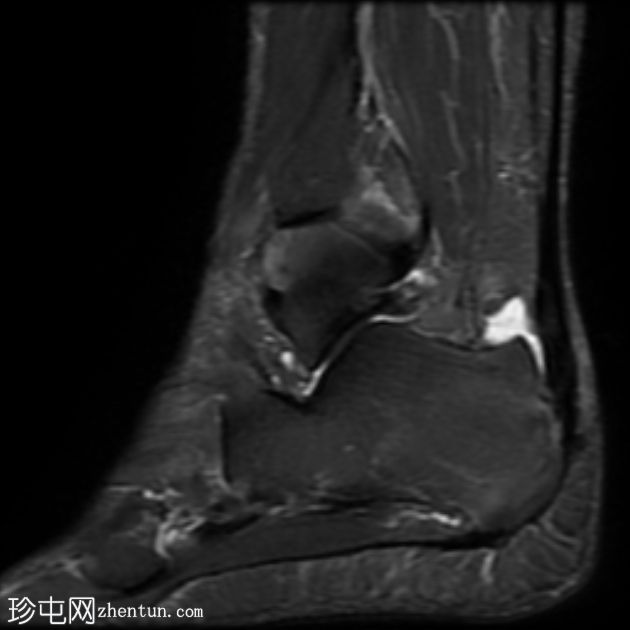

MRI

矢状位

T1

T2

STIR

跟腱插入

,伴有跟腱明显增厚,可诱发异常信号、跟腱后滑囊炎、跟骨后突及骨髓水肿信号。

Haglund综合征的检查结果令人印象深刻。

Haglund综合征是指以下三联征(Haglund三联征):

跟腱插入性病

跟腱后滑囊炎

Haglund畸形(即跟骨后上外生骨疣)